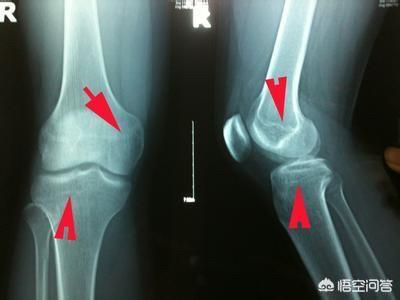

Medizinisch gesehen kann man nach der Menstruation noch größer werden, solange sich die Epiphyse nicht geschlossen hat. Wenn Sie wirklich wissen wollen, ob Sie noch größer werden können, gehen Sie am besten ins Krankenhaus und lassen Sie Ihr Knochenalter mit einem Ultraschall untersuchen. Solange Ihr Knochenalter Ihr Alter nicht übersteigt, haben Sie das Potenzial, größer zu werden.

Deshalb, wenn das Mädchen hat seit einem Jahr menstruiert, nach dem normalen ist bereits späte Entwicklung, können Sie das Kind zu einem Knochenalter zu überprüfen, wissen, ob das Kind Epiphyse geschlossen ist, wenn es geschlossen wurde, dann ein halbes Jahr nicht wachsen, was bedeutet, dass aufhören zu wachsen größer.